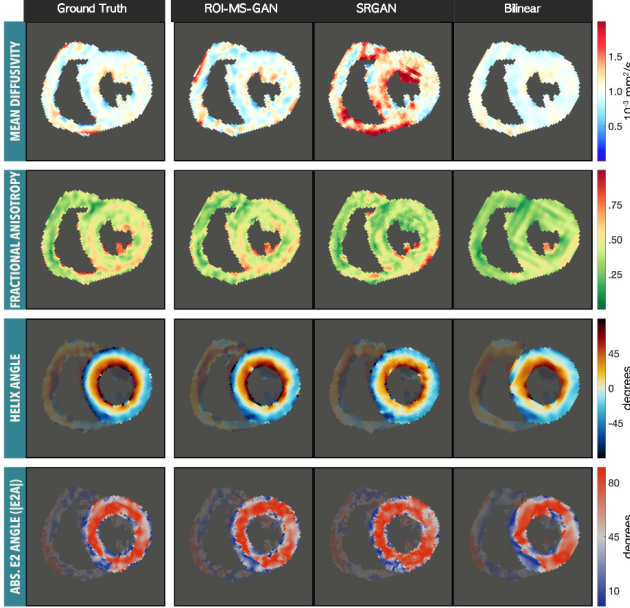

Smart Imaging and Analysis for Cardiovascular MR

A novel deep learning-based and ROI focused multi-scale super-resolution approach is proposed to improve the apparent spatial resolution of in vivo Diffusion Tensor Cardiovascular Magnetic Resonance (DT-CMR).

A novel deep learning-based and ROI focused multi-scale super-resolution approach is proposed to improve the apparent spatial resolution of in vivo Diffusion Tensor Cardiovascular Magnetic Resonance (DT-CMR).